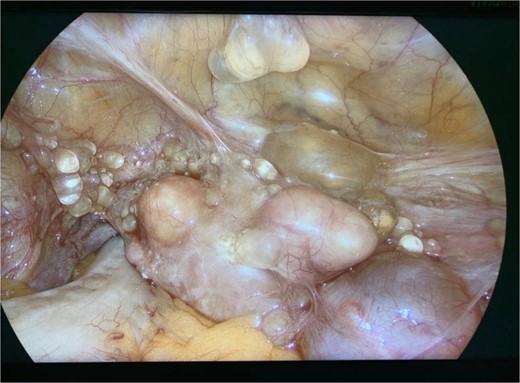

Diagnostic laparoscopy demonstrated multiple cystic lesions throughout the abdomen and pelvis (Figs 3 and 4). The gross appearance of these cysts was consistent with mucinous carcinomatosis. Laparoscopic excisional biopsy of several lesions was performed. Frozen section analysis revealed mucin but did not reveal evidence of metastatic adenocarcinoma. Colectomy was deferred due to concern for carcinomatosis, as if confirmed, she would likely be treated with neoadjuvant chemotherapy, restaging, followed by cytoreductive surgery (to include synchronous right colectomy) with heated intraperitoneal chemotherapy.

Intraoperative view of the right lower quadrant of the abdomen: cysts involving peritoneum of the right colon and mesentery.

Intraoperative view of the pelvis: multiple cysts involving the peritoneum.